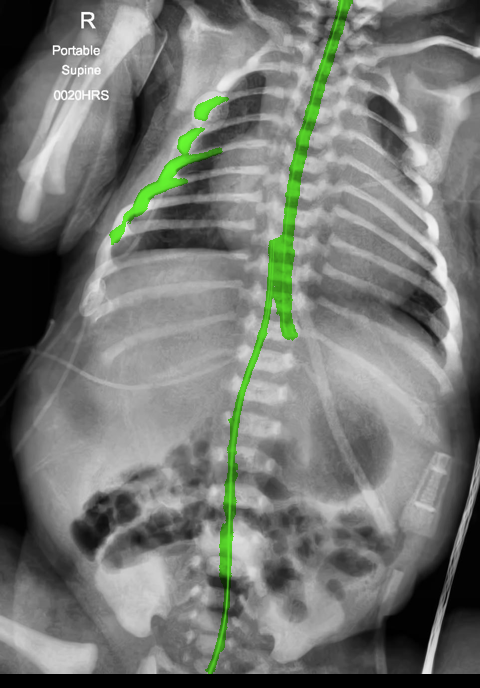

There are certain situations where our proposed method would fail. Figure 7 (a) and (b) show a partially detected NGT. This mostly likely resulted from the decreased visibility of the radiopaque strip. Figure 7 (a) also shows another failure situation where the inferior portion of the UVC is occluded by the abdomen. (c) shows the case of a falsely detected unidentified line and (d) shows part of the lateral aspect of the rib cage falsely identified as a catheter.